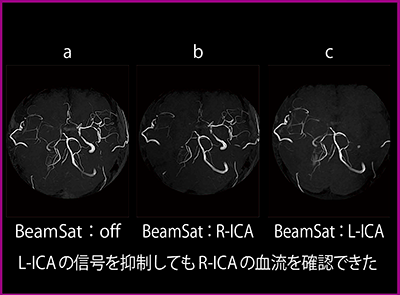

術前MRAのMIP画像のBeamSatなし(図5 a)では,R-ICAに狭窄所見はあるものの,R-MCAはわずかに描出される。R-ICAにBeamSatを印加すると,R-MCAが左内頸動脈(L-ICA)系からウィリス動脈輪を介して描出されていることがわかる(図5 b)。L-ICAにBeamSatを印加すると,R-MCAを含めたウィリス動脈輪より末梢の血管が描出されないことから,ウィリス動脈輪の血流はL-ICAに頼っていることがわかる(図5 c)。

また,血管造影との比較では,R-ICAにBeamSatを印加した画像とL-ICA造影画像は,ウィリス動脈輪より末梢の血流が同じように描出された。なお,L-ICAにBeamSatを印加した画像とR-ICA造影画像は,共にR-ICA狭窄が認められたが,前者では椎骨脳底動脈系から後交通動脈を介してR-MCAの描出を確認できたのに対し,後者では判断できなかった。